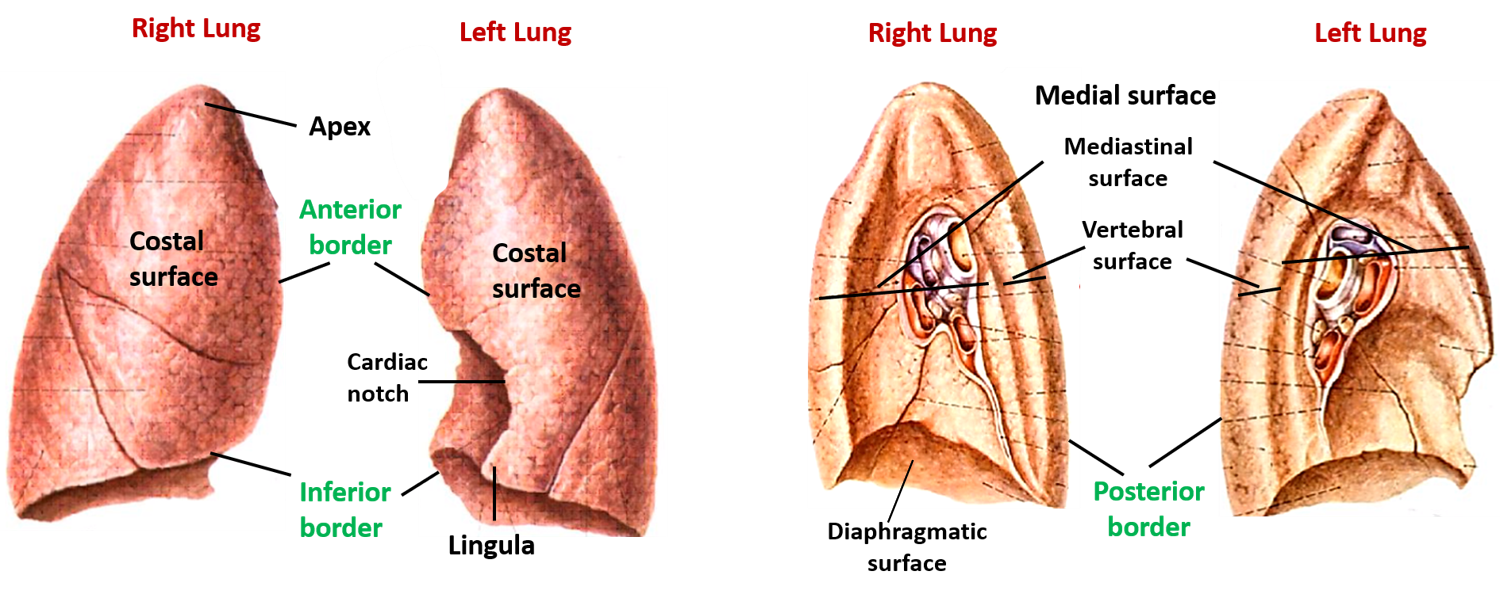

Lungs – Anatomy QA

lung lingula anatomy lungs mediastinal posterior medial vertebral surfaces hilum anatomyqa

Lungs lobes fissures right left oblique both teachmeanatomy lung structure thorax fig similar position info. Pin on bronchial anatomy. Topography of the lungs (posterior view) the apex of the lung extends